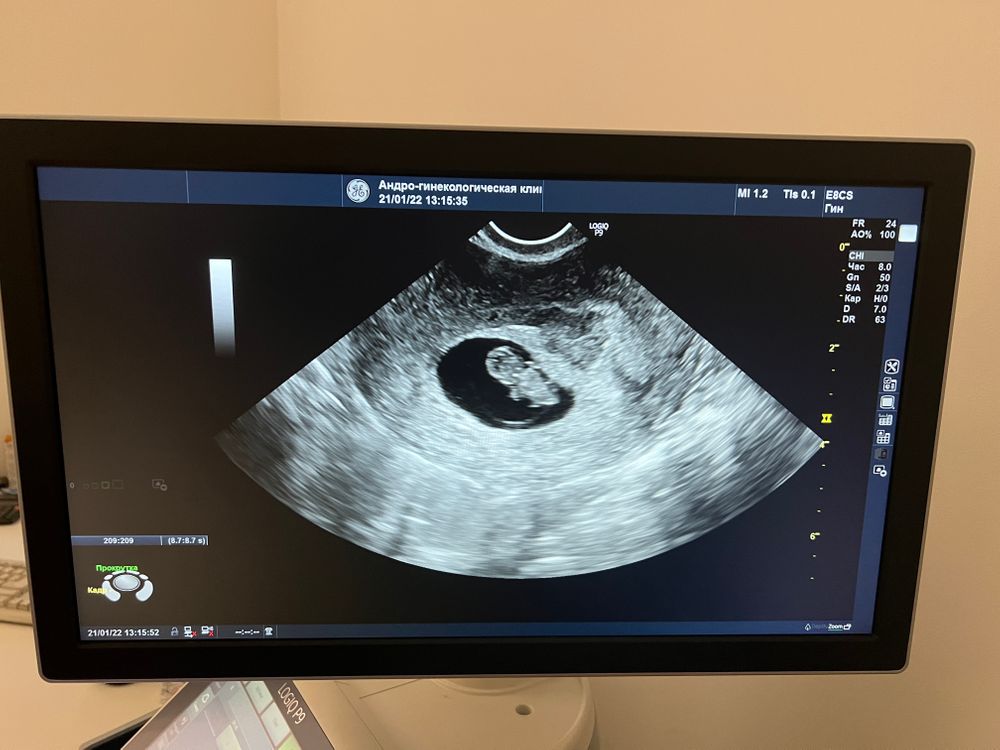

Сегодня сделала полное узи со всеми размерами 🥰 все наши сроки совпадают, мой классный Бобби даже ручками дрыгал😂🤤сладкий ребёнок 🤤 так вышло, что передо мной муж узи почек делал и остался 😁 впервые увидел такого маленького человека, аж растерялся 😂😁сейчас ходит сияет, я говорит Бобби своего видел 😍😄 девочки, пусть у каждой в животике растёт маленькое счастье , которое будет совпадать по всем срокам 🙏 те, кто на пути, пусть ваш путь скорей увенчается счастьем в виде пупса. Я до сих пор не верю, но уже осознаю, во мне бьется маленькое сердце 💓🤤

Меня вот тоже на этом сроке очень поразило узи, там руки шевелятся и ноги 😆

Эти танцы в 8 недель меня тоже поразили, лежит там себе, дрыгается чего-то😀 ну прелесть же

Victoria Sever, 😄😂 классные не могу 🤭😁😍 я что то по ктр сейчас заморочилась 🤔 15мм для 8.0 норма? Что-то как будто по таблицам должно быть чуть больше

Victoria Sever, когда мы научимся просто расслабляться и слушать врачей, а не искать причины для интрижек😄🤦🏽♀️😮💨 да, врач сказала, я все очень хорошо рассмотрела, все вообще прекрасно.. и по малышу и по мне ттт 💦💦💦🤞🏽Ещё и написала ктр соответствует сроку 8+2

Любовь Александровна, ну видите, даже опережает, так что всё хорошо точно. на этих сроках уже сам аппарат УЗИ срок выставляет по размеру КТР)